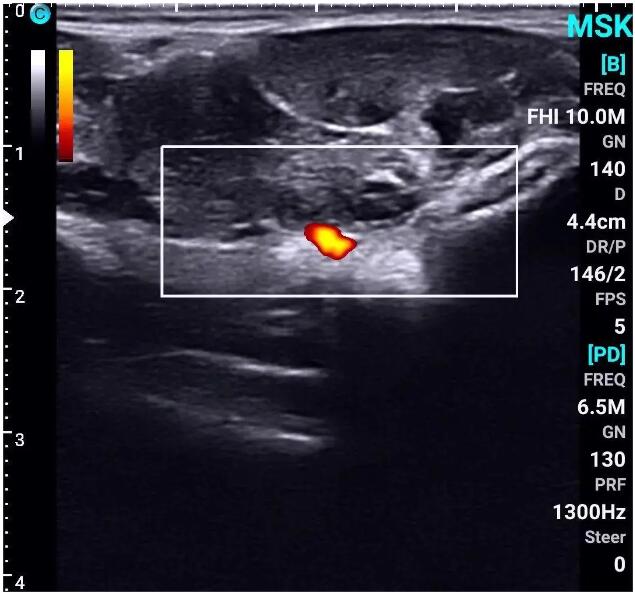

The application of handheld ultrasound technology provides more precision and safety for plastic surgery, improving treatment outcomes and patient satisfaction.

Vascular and Nerve Localization: Using ultrasound pre-procedure to locate important blood vessels and nerves can help avoid damaging these structures during procedures, reducing the risk of complications.

Precise Injection: When performing injections of fillers, botulinum toxin, etc., handheld ultrasound can help doctors avoid critical blood vessels and nerves, reducing the risk of complications and improving the safety and efficacy of injections.

Real-time Monitoring: During the injection process, the distribution of the filler can be monitored in real-time, ensuring even placement and preventing unnecessary displacement or over-injection.